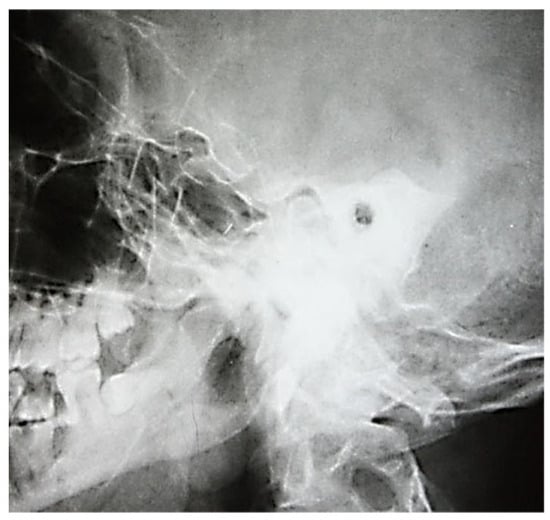

3.1. Analyzing the Results of Radio-Imaging Investigations

3.1.1. Conventional Radiology

3.1.2. Computed Tomography and Magnetic Resonance Imaging